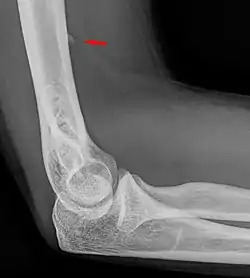

![]() Small supracondylar process seen on a lateral radiograph of the elbow | |

The supracondylar process of the humerus (also known as an avian spur) is a variant bony projection on the anteromedial aspect of the upper arm bone (humerus), about 5–6 cm above the medial epicondyle.[1] It is directed downward, forward and medially pointing to the medial epicondyle. A fibrous band, Struthers ligament, may connect this process to the medial epicondyle.[2] This variation has a prevalence of 0.68% and is significantly more common in women than in men.[3]